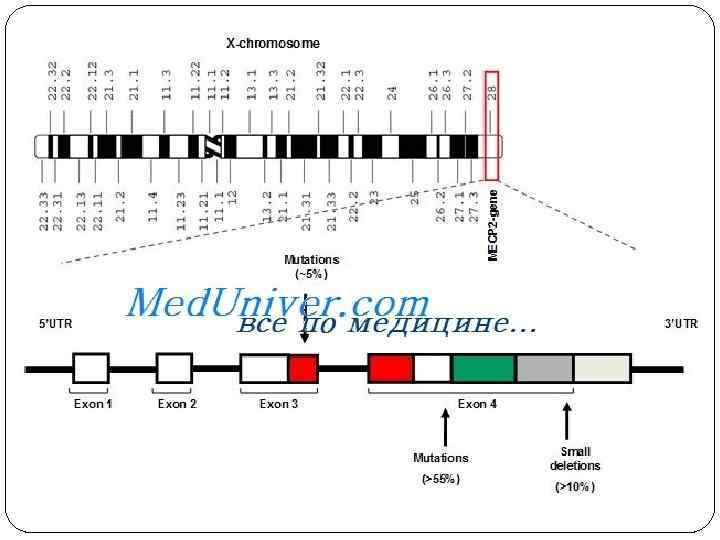

ЭТИОЛОГИЯ Синдром является генетическим заболеванием. К заболеванию приводят мутации в гене МЕСР 2. Этот ген кодирует метил-Ср. G-связывающий белок 2(Ме. СР 2). Если ген нормален, его белок в определённый момент развития мозга выключает из работы несколько других генов, и тогда мозг ребёнка развивается нормально. Если же ген поврежден мутацией, своевременное выключение не происходит. Мозг, пропустивший этот момент, начинает развиваться неправильно. Так возникает синдром Ретта. Ген Ме. СР 2 находится в X-хромосоме. Поскольку у женщин таких хромосом две, женские плоды с синдромом Ретта обычно обладают одним нормальным и одним дефектным геном, что позволяет им дожить до рождения. У мужчин имется только одна X-хромосома. Если она несет дефектный ген МЕСР 2, то у плода не остаётся нормальной копии гена, и он чаще всего погибает. Поэтому мальчики с синдромом Ретта рождаются очень редко. Несколько известных случаев болезни у мальчиков сопровождались синдромом Клайнфельтера с полисомией XXY, то есть одной лишней X-хромосомой.